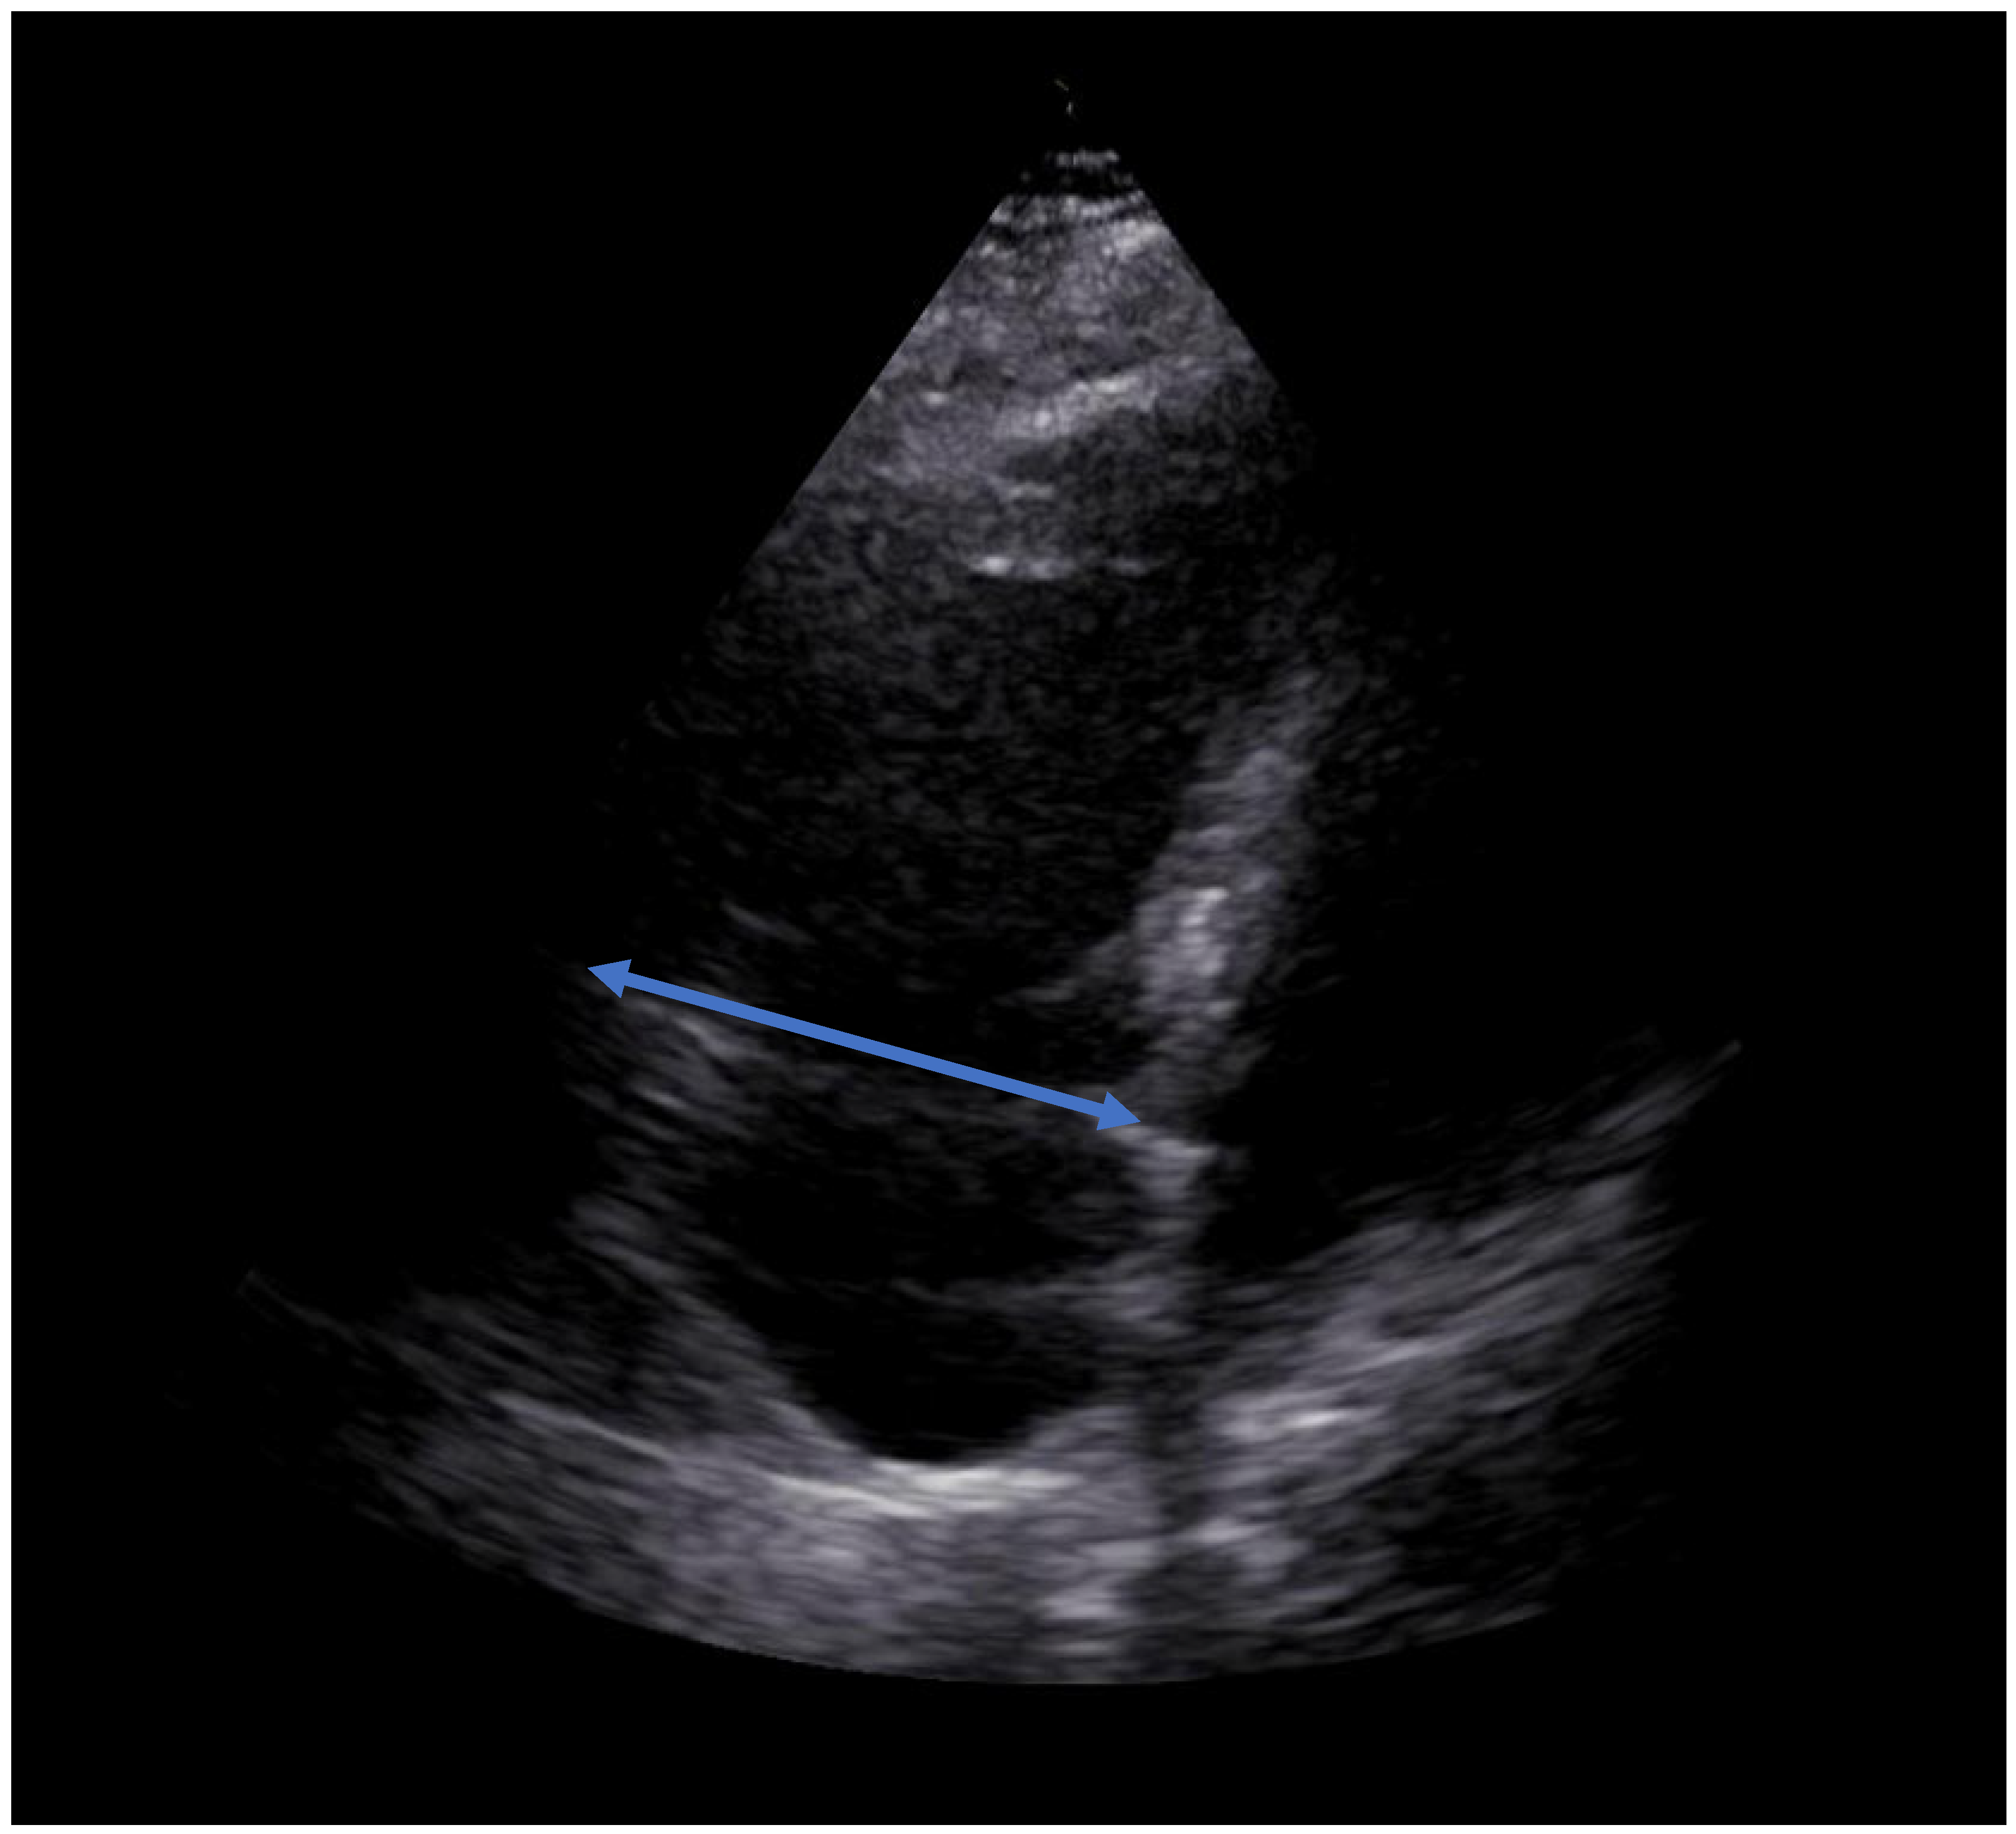

| RVEDD [mm] | 65 | 49 | 37 |

| D- Sign | Yes | No | No |